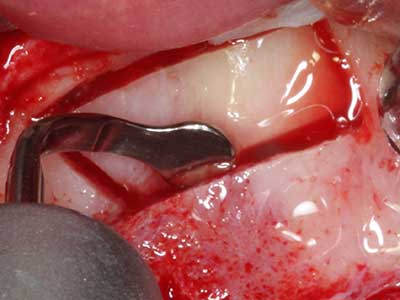

Abb. 17a: CT-Aufnahme eines wachstumsprogredienten Osteoms in unmittelbarer ...

Abb. 17b: Lagebeziehung zum Alveolarkanal mit Nervirritation (laterale und koronare Ansicht).

Abb. 18: Präparation eines Kortikalis-Deckels mit der Piezo-Knochensäge (Piezomed, W&H).

Abb. 19: Operationssitus nach Neurolyse und Osteomentfernung.

Abb. 20: Der entnommene Knochendeckel wird readaptiert und durch eine Osteosyntheseschraube (KLS Martin, Tuttlingen) fixiert.